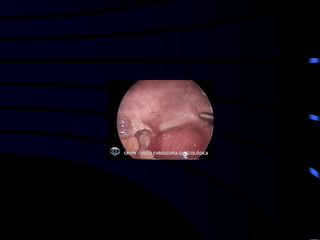

• Cirurgia (VIDEOLAPAROSCOPIA)

 A laparoscopia é ideal para diagnóstico e

tratamento do abdome agudo ginecológico